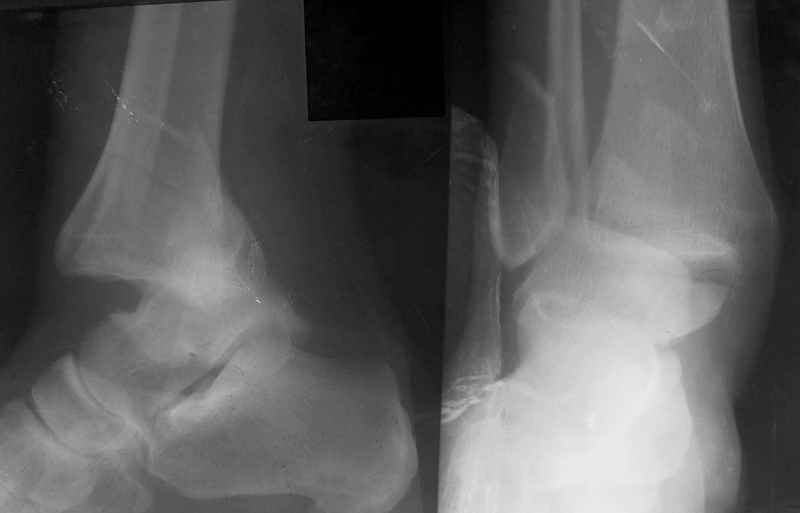

День-вечер добрый ,Никита.Ваш случай представляется мне довольно типичным,хотя возможно, я чего-то не замечаю.

Мне кажется,что стояние отломков достаточно хорошее,но следует уменьшить дистракцию на 1.5-2мм.Имея опыт лечения подобных переломов могу сказать следующее:

> 1. Уменьшать ли высоту суставной щели голено-стопного сустава?

> Перестарался я, добиваясь сопоставления дистального отломка

> малоберцовой кости по длине.

Ответы на вопросы: 1. Дистракцию снять! Все правильно вы понимаете: наружная лодыжка -ключ г\ст сустава, а пытаетесь наоборот - таранную кость сделать "ключом"... Нейротрофические расстройства очень могут появиться..